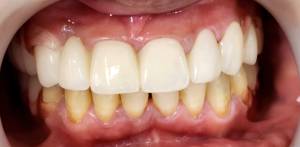

After Treatment (The Result)

After completion of treatment, the patient showed:

• Improved dental appearance

• Replacement of missing teeth

• Better chewing comfort

• Improved bite balance and vertical dimension

After-treatment images